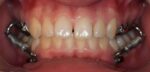

Klasse III-elastieken kunnen worden bevestigd tussen bolderankers op de bovenkaak en in het hoektandgebied van de onderkaak bij jonge, opgroeiende patiënten. Door het uitrekken van de circummaxillaire hechtingen wordt de voorwaartse groei van de bovenkaak vergroot , wat resulteert in een anterieure rotatie van het jukbeen-maxillaire complex. Dankzij de skeletverankering is de mate van protractie van het middengezicht ongeveer het dubbele van de mate van protractie die wordt verkregen met een gezichtsmasker.

Uit nieuw bewijsmateriaal blijkt echter dat ook de kin naar achteren kan worden bewogen zonder achterwaartse rotatie van de onderkaak, dankzij modelleringsprocessen aan de ramus en sluiting van de goniale hoek. Bovendien wordt bij het modelleren van de glenoïdfossa de onderkaak iets naar achteren geherpositioneerd. De combinatie van groeimodificaties van de bovenkaak en de onderkaak kan resulteren in een belangrijke verbetering van de gezichtsesthetiek, ook bij schisispatiënten.